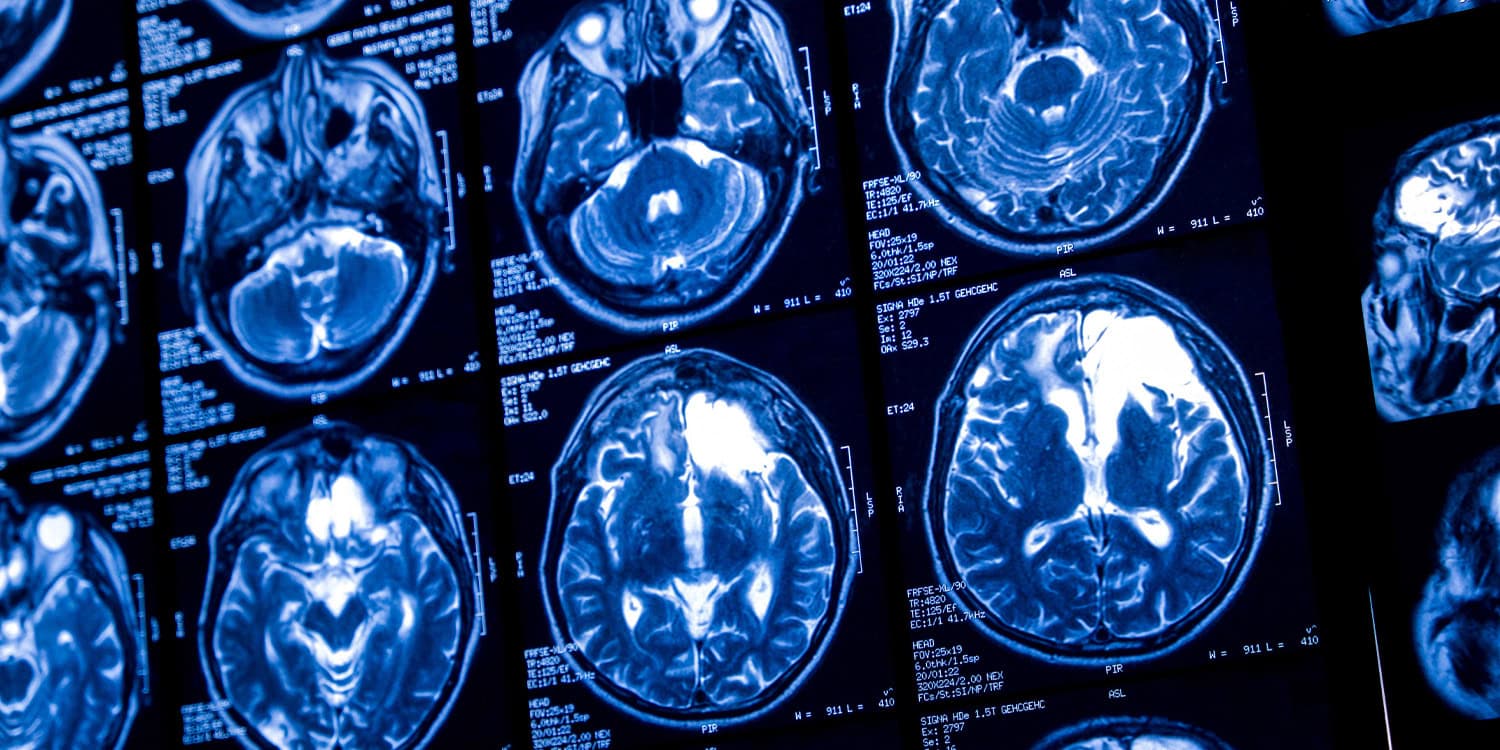

The participants filled out detailed questionnaires about their drinking habits over the last year, three years, and throughout their lives. They then underwent magnetic resonance imaging scans.

These scans enabled researchers to gauge the volume and thickness of the cerebral cortex, the brain’s outer layer linked to higher-level cognitive processes. For the perfusion group, the scans also measured active blood flow in differing brain areas.